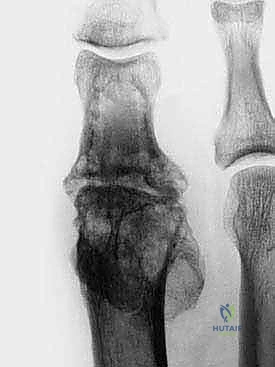

2. النخر اللاوعائي (Avascular Necrosis - AVN)

حالة يموت فيها جزء من رأس العظم المشطي بسبب انقطاع التروية الدموية عنه. قد يحدث هذا بعد صدمة شديدة، أو كمضاعفات لجراحة سابقة، أو لأسباب مجهولة. يؤدي موت العظم إلى انهياره وتفتته، مما يترك فجوة كبيرة تتطلب التطعيم العظمي.

2. تحضير الأسطح العظمية (Preparation of Bone Ends)

هذه الخطوة حاسمة. يجب إزالة جميع الغضاريف المتبقية، والعظام المتصلبة (Sclerotic bone)، والأنسجة الميتة حتى يتم الوصول إلى عظم إسفنجي صحي ينزف (Bleeding cancellous bone). هذا النزيف ضروري لتوفير الخلايا الجذعية وعوامل النمو التي ستساعد في التئام الطعم العظمي.

5. تشكيل وزرع الطعم العظمي (Shaping and Inserting the Graft)

يتم نحت الكتلة العظمية بدقة لتتناسب تماماً مع الفجوة. يمكن استخدام تقنية القطع المسطح (Flat cuts) أو تقنية الكرة والمقبس (Ball and socket) لزيادة مساحة التلامس وتعزيز الاستقرار. يتم إدخال الطعم في الفجوة، مما يعيد للإصبع طوله ومحاذاته الميكانيكية فوراً.